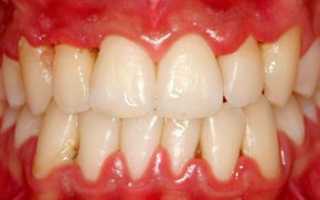

Каждая из форм хронического воспаления имеет свои отличительные особенности. Для катарального хронического воспалительного процесса характерно затяжное течение, при этом отмечается незначительная отечность десневой ткани, гиперемия слизистой оболочки, кровоточивость десен при механическом раздражении. Больной жалуется на неприятный запах из ротовой полости, наблюдается ускоренное образование зубных отложений.

Для гипертрофической формы хронического воспалительного поражения десневой ткани характерно увеличения объема десен, которое происходит за счет гипертрофического разрастания верхних слоев пародонта. Отечная форма хронического гипертрофического гингивита характеризуется сильным покраснением и отечностью десен, их болезненностью при пальпации, термическом и механическом воздействии. Фиброзная форма хронического гипертрофического гингивита характеризуется образованием ложных зубодесневых карманов.